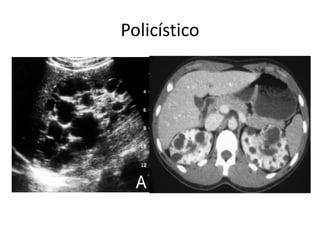

Cístico (Simples)

Policístico